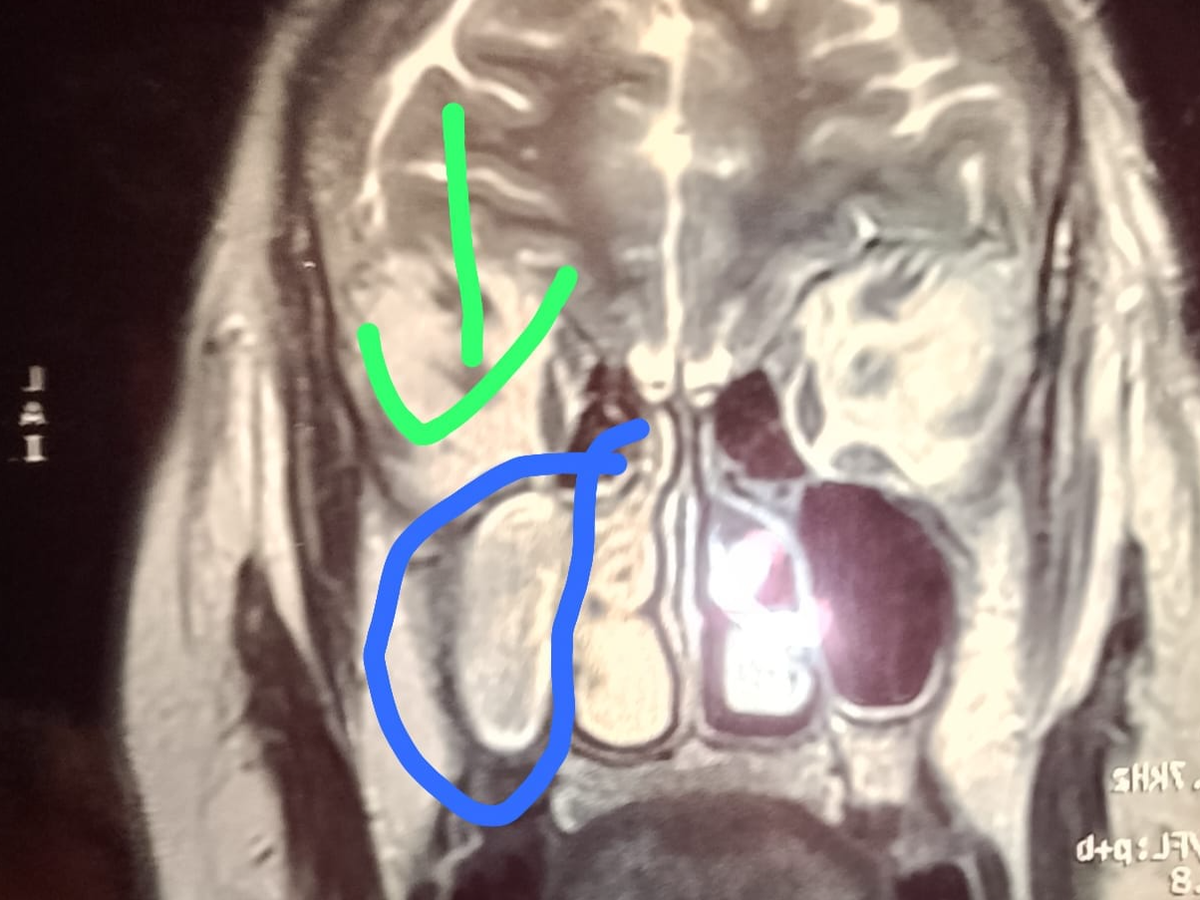

Hola, me llamo Claudia y estoy recaudando fondos para cirugía de craneo de mi mamá, en Cd. Juárez, le creció un tumor y oprimio nervio óptico del lado derecho el cual hizo que perdiera la vista de ese ojo. Hace más de un año está esperando cirugía por medio del IMSS, la cual no se a realizado por falta de equipo, viajo en 2 ocasiones ala ciudad de Torreón y ya estando en quirófano se canceló por falta de un aparato. Acudió a neurocirujano y comenta que si no se opera seguirá oprimiendo y es de riesgo ya que está en una arteria, es cirugía urgente la que necesita mi mamá ya que su vida corre peligro.